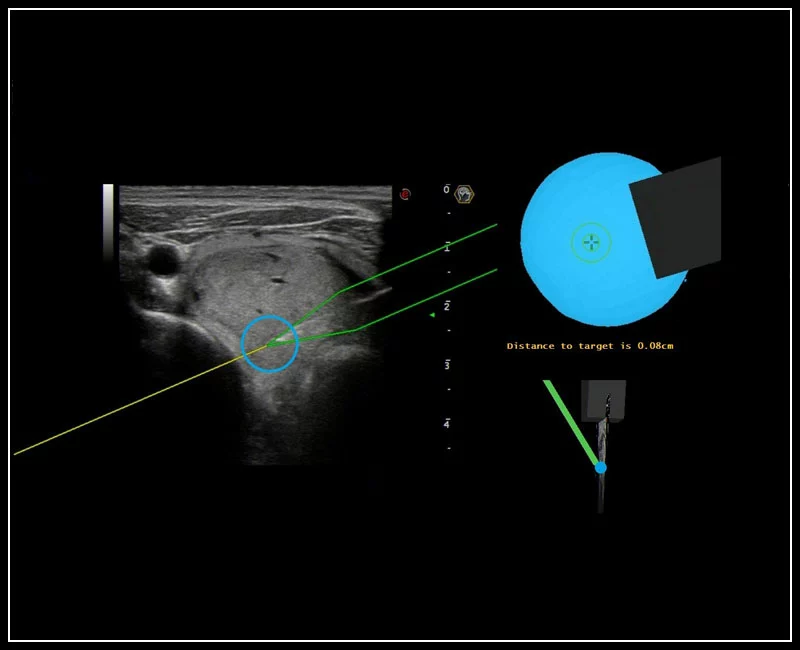

MyLab™9 Platform - Precise lesion detection and guidance with Virtual Biopsy

MyLab™9 Platform - Precise lesion detection and guidance with Virtual Biopsy